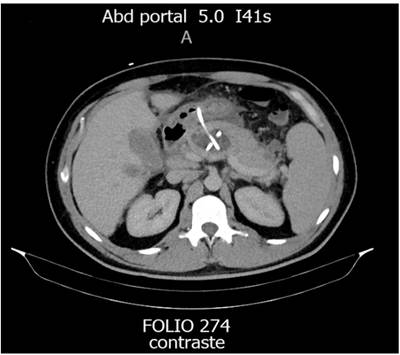

En relación con las características de los pacientes, 5 eran hombres con media de edad de 39 años. Todos los pacientes presentaron NPI como indicación inicial para el drenaje percutáneo. Los abordajes percutáneos para el tratamiento de la NPI fueron el transgástrico, transperitoneal y transretroperitoneal guiado por imágenes, combinándolos dependiendo cada caso clínico (Figura 1 y 2, Tabla 1).

Se utilizaron catéteres multipropósito pigtail, entre 10 y 12 Fr. El tiempo promedio de resolución de la NPI fue de 42 días.

En cuanto al diagnóstico de la DDP, 4 fueron mediante tomografía axial computarizada (TAC) y 2 por resonancia magnética (RM). Como resultado, se obtuvieron 4 (66,6 %) DDP parciales y 2 (33,4 %) totales. Todas las DDP se ubicaron en el cuerpo del páncreas.

Debido a que la DDP no se resolvió con tratamiento médico con octreotida y nutrición parenteral total durante el lapso de 14 días, se colocaron diferentes prótesis utilizando el trayecto del catéter transgástrico. Las prótesis utilizadas fueron: 2 stents biliares doble J (33,4 %), 1 catéter doble J (16,6 %), 1 catéter pigtail invertido (16,6 %) y 2 internalizaciones de catéter transgástrico (33,4 %). Cabe resaltar que en los 2 casos de DDP total se utilizaron un stent biliar doble J y un catéter doble J urológico.